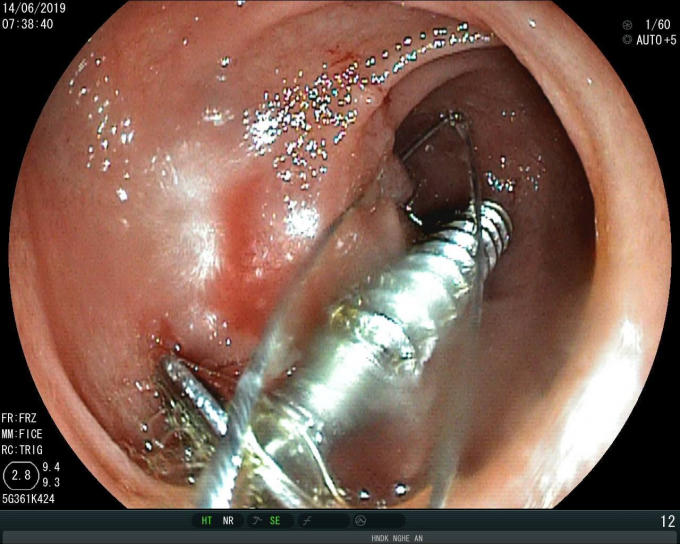

Trước đó, vào ngày 14/6, bệnh viện Hữu nghi đa khoa Nghệ An tiếp nhận bệnh nhi Ng.H.H (20 tháng tuổi) với chẩn đoán nuốt phải dị vật kim khí. Kết quả nội soi cho thấy, tại đoạn cuối tá tràng của bệnh nhi có hình ảnh dị vật kim loại một đầu sắc nhọn (ốc vít kim loại) dài 3,5 cm. Chiếc đinh vít có một đầu rất sắc nhọn có thể đâm thủng ruột, dạ dày của trẻ, gây nguy hiểm đến tính mạng.

Ngay sau đó, các bác sĩ đã tiến hành nội soi gắp dị vật ra ngoài an toàn bằng phương pháp thòng lọng.

Chiếc đinh vít được nội soi đưa ra ngoài an toàn.